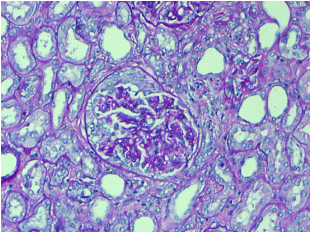

With hydration, his clinical status improved as he started to eat and take fluids orally. His fatigue improved. Clinically looked euvolemic. In addition to this, his BUN and creatinine improved to 89 mg/dl and 7.3 mg/dl, respectively. Considering his AKI was most likely secondary to volume depletion with signs of improvement, he was discharged, however, ANCA levels were sent and pathology slide from his RCC specimen was requested for review for any possible glomerulopathy. Histopathology of the uninvolved renal parenchyma examined by Periodic Acid Schiff (PAS), silver and trichome stains showed rare glomeruli with segmental fibroid tuft necrosis and cellular crescent (Figure 1,2,3). There was patchy chronic interstitial inflammation and tubular injury. Later ANCA levels came out to be 1:640 positive for PR3 (level was 1115). He was managed with IV Methylprednisolone 500 mg for 3 doses followed by Prednisone 60 mg with a plan to taper over the next 6 months and Rituximab 375 mg/m2 weekly total of 4 doses. Over 4 weeks follow-up with completion of Rituximab, his creatinine declined to 2.5mg/dl, UA showed 6-10 RBC with UPCR of 0.5.

Figure 3. Glomerulus with cellular crescent. No hypercellularity or mesangial expansion was present in the tuft. PAS, 200X